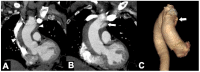

Non-traumatic thoracic aorta emergencies are associated with significant morbidity and mortality. Diseases of the intimomedial layers (aortic dissection and variants) have been grouped under the common term of acute aortic syndrome because they are life-threatening conditions clinically indistinguishable on presentation. Patients with aortic dissection may present with a wide variety of symptoms secondary to the pattern of dissection and end organ malperfusion. Other conditions may be seen in patients with acute symptoms, including ruptured and unstable thoracic aortic aneurysm, iatrogenic or infective pseudoaneurysms, aortic fistula, acute aortic thrombus/occlusive disease, and vasculitis. Imaging plays a pivotal role in the patient's management and care. In the emergency room, chest X-ray is the initial imaging test offering a screening evaluation for alternative common differential diagnoses and a preliminary assessment of the mediastinal dimensions. State-of-the-art multidetector computed tomography angiography (CTA) provides a widely available, rapid, replicable, noninvasive diagnostic imaging with sensitivity approaching 100%. It is an impressive tool in decision-making process with a deep impact on treatment including endovascular or open surgical or conservative treatment. Radiologists must be familiar with the spectrum of these entities to help triage patients appropriately and efficiently. Understanding the imaging findings and proper measurement techniques allow the radiologist to suggest the most appropriate next management step.